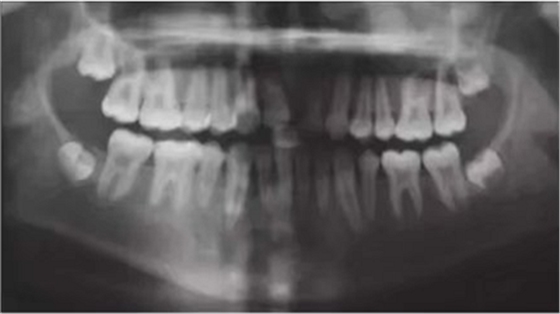

6個(gè)月后,移植牙的根尖片顯示治療期間沒(méi)有出現(xiàn)牙根吸收的影像?;颊邲](méi)有出現(xiàn)不適,沒(méi)有發(fā)生牙齦炎。在23個(gè)月期間沒(méi)有進(jìn)行任何修復(fù)完成治療,達(dá)到I類關(guān)系(圖5和圖6)。

【病例分享】上頜中切牙區(qū)外傷的自體移植和正畸治療

圖5. 正畸后影像學(xué)檢查

圖6. 正畸后口內(nèi)照